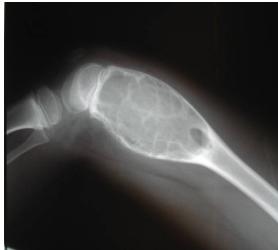

Other Metaphyseal Lesions

Popcorn, cartilaginous - chondrosarcoma usually - even though theres no perosteal reaction